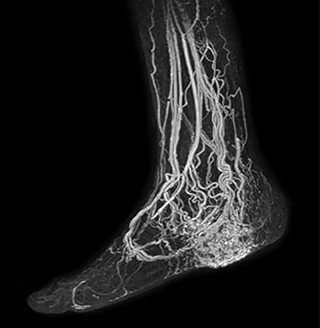

MRA of foot with 4D-TRAK XD

The images obtained with Ingenia Ambition show large coverage and high uniform signal. More vessels are visible than in a previous exam of the same patient on Achieva. The movies show a higher temporal resolution in the Ambition acquisition than in a previous Achieva 1.5T exam. Both exams use a FOV of 300 mm and voxel height and width of 0.78 mm.

4D Trak XD 1:54 min. TE 1ms, TR 3ms

Another example is the foot examination for diabetic patients, which has improved dramatically. “The forefoot is generally difficult to image with MRI because of the inhomogeneities that the toes create – it’s hard to obtain good fat saturation in that area. Here, mDIXON made a huge difference right away, we obtain much better image quality,” Dr. Peña says. “Using mDIXON, Compressed SENSE and the dS FootAnkle coil, we have been able to reduce the scan time, so that we can now also include an additional 3D STIR sequence to visualize both arteries and veins in the foot.”

Avila adds: “In addition, since most of these patients are in a significant amount of pain, it’s important to perform the examination as quickly as possible. With Compressed SENSE and mDIXON we have been able to reduce the scan time from about 45 minutes to just 15 minutes. Not only does this improve patient comfort, we see that it also helps us acquire images without motion artifacts, which is critical to making a confident diagnosis.”